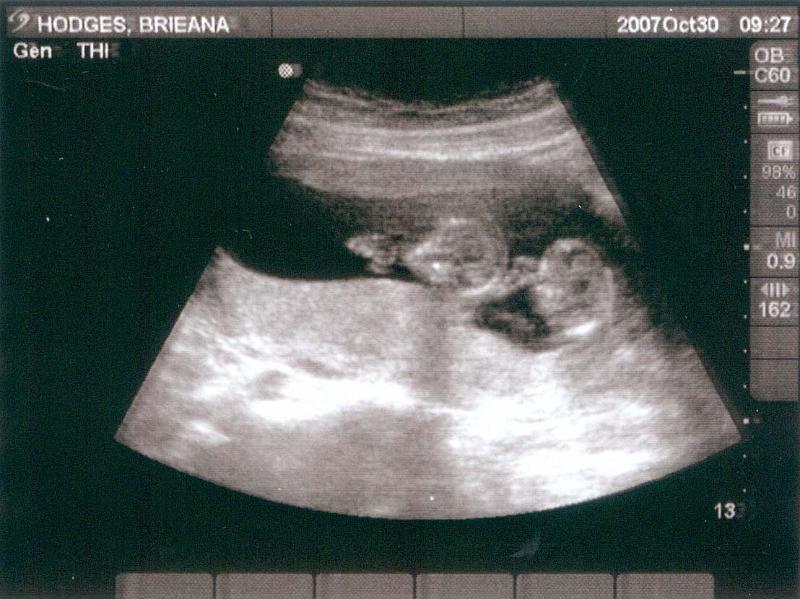

Up trejo twins » just born » ultra sounds Prev Next Slideshow